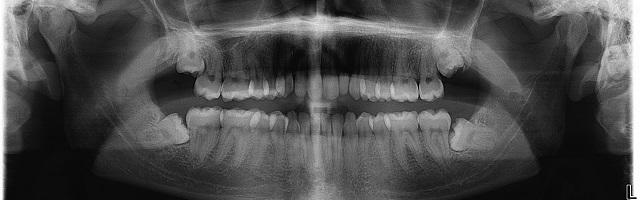

Wisdom teeth are jokingly called the dentists best friend: they almost always need to be removed or have some kind of problem with them. In this article we wish to go about explaining why wisdom tooth pain and wisdom tooth issues are so frequent, and what kind of issues they are. We also wish to describe the different kinds of problems that frequently occur with wisdom teeth, and thus can prepare you for what you may experience.